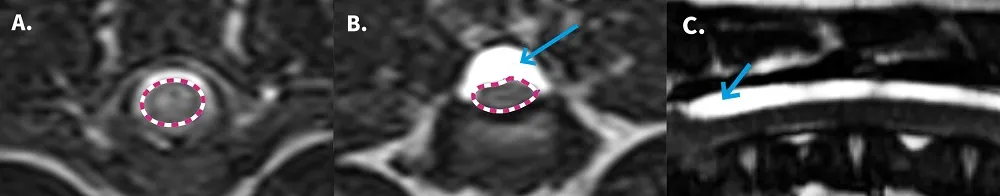

A selection of MRI images. Comparison of [A] normal spinal cord (dotted red circle) and [B] Geralt’s compressed spinal cord (dotted red circle) due to the build-up of cerebrospinal fluid (highlighted by the blue arrow). [C] Geralt’s spinal arachnoid diverticulum (highlighted by blue arrow) running along his spinal cord.